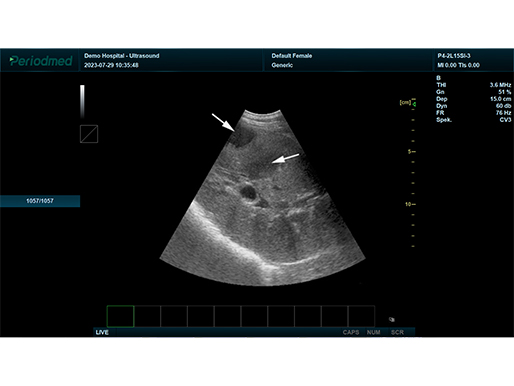

有关病变的更多见解

B模式 肝右叶 马

有关病变的更多见解

凸阵探头-B模式-肝右叶 马